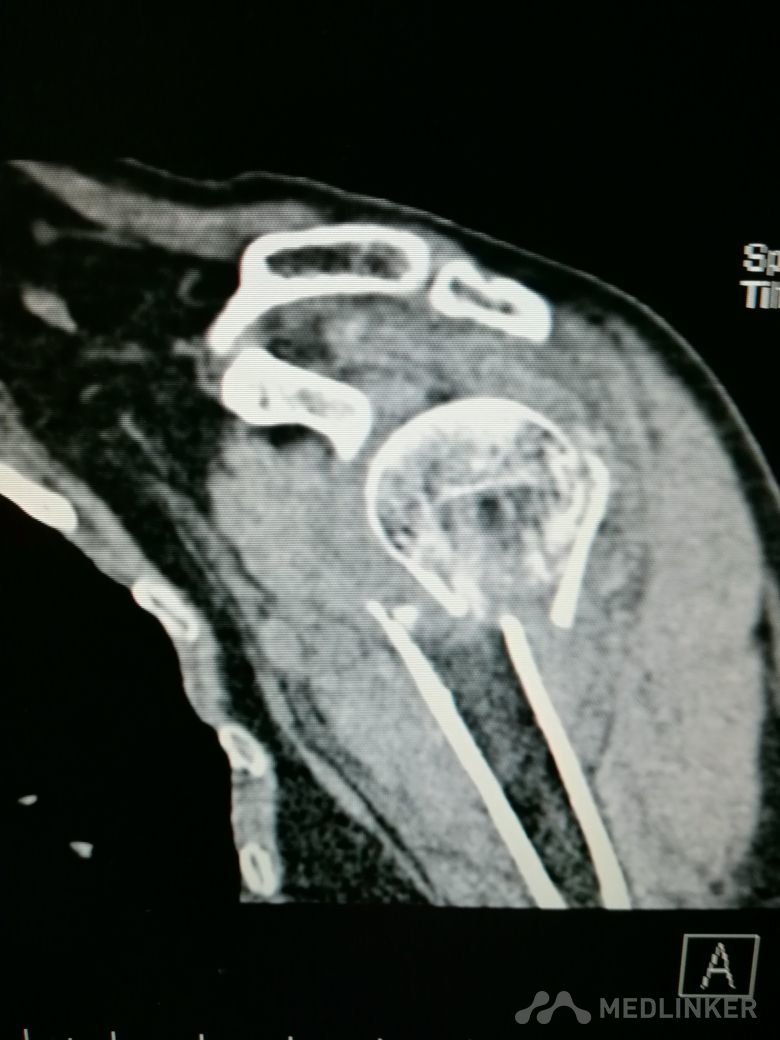

肱骨近端骨折 Neer IV型

患者,女性,55岁,因外伤致左肩疼痛六小时入院,既往无其他慢性病史

查体 右肩肿胀,畸形,活动受限,压痛,皮下淤血,右桡动脉搏动存在

完善相关检查,在腰麻下行右肱骨近端骨折切开复位内固定术

肱骨近端骨折占到肱骨骨折的45%,肱骨近端锁定钢板具有低切迹、高弹性、生物力学性能优良等特点,可以起到角度稳定控制旋转的作用。但是对于严重粉碎性肱骨近端骨折而言,单纯的肱骨近端锁定钢板不一定能够提供稳定的固定,手术之后仍有可能出现内翻塌陷、前后成角、螺钉切出、骨折畸形愈合、骨折不愈合等并发症。